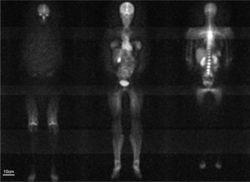

imgi_183_250px-Whole-body_sodium_magnetic_resonance_images_of_female_human.png